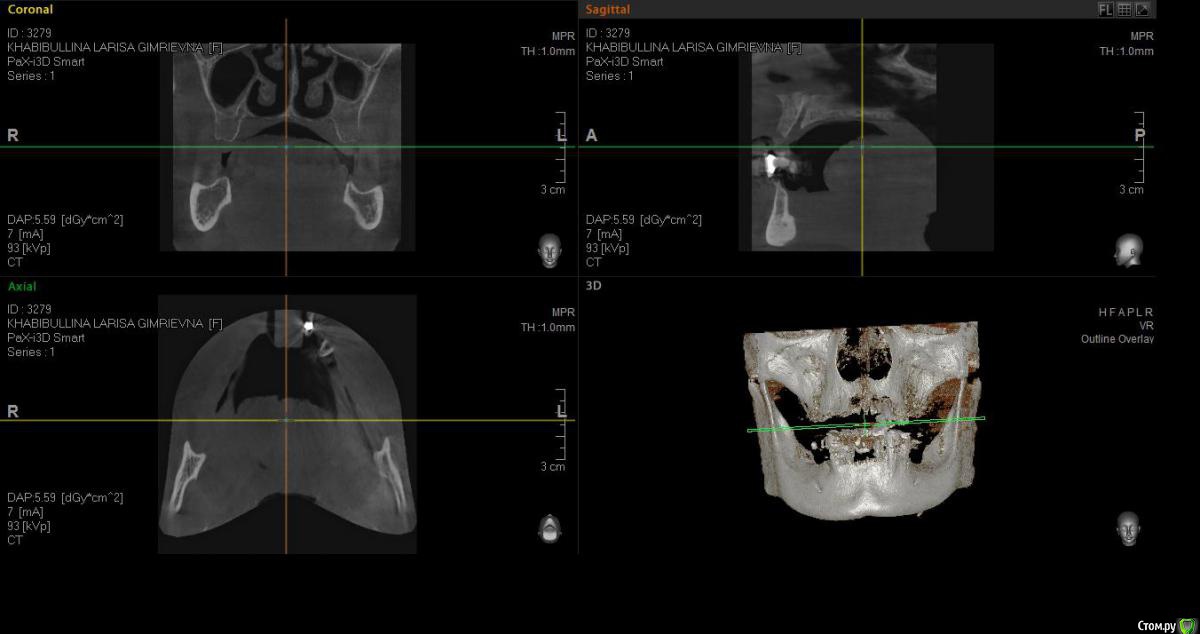

Реальная картина на сегодня:

1.        Верхняя челюсть – полная адентия (имеется один корень клык)

2.        Нижняя челюсть – протез просел – в коррекции отказано, (с левой стороны протез держится на отдельно стоящем подвижном зубе, т.к. распалось соединение с зубным рядом.)

- Нижняя челюсть выдвинулась в перед (возрастной мезиальный прикус)

- Нижняя челюсть гипермобильна , дисфункция ВНЧС, хрустит прикус прогенически,  (диагноз ЧЯХ (в лечение отказан) Рот открывается рывком (безболезненно)

- Нужно ли наращивать кость в челюсти?

1. Сильно выдвинулась челюсть. Вопрос – можно ли с помощью имплантации (с несъемной конструкцией) исправить прикус и остановить процесс выдвижение нижней челюсти.

2. Достаточно ли кости для проведение имплантации? Нужна ли ринопластика?

5. Если имплантанты на верхней челюсти будут установлены под определенным углом, не скажется ли это негативно на прочности конструкции?  Достаточно ли 6 имплантантов на верхнюю челюсть?